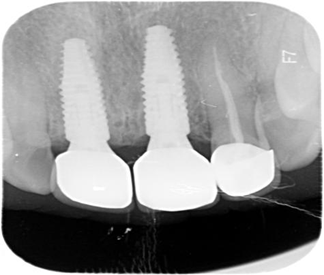

▲CT影像图(显示骨高度12mm、骨宽度8mm)

CBCT三维影像显示的检查结果出来了:

11、21号牙冠体完全脱落,残留牙根骨吸收严重,像风化的枯木;叩击无痛感,牙龈未红肿,冷热测试毫无反应,结合电活力测试后确认牙髓坏死;牙槽骨宽度8mm,无急性感染,且骨量充足,符合即刻种植条件……

"牙根在根管治疗后已失去营养供应,现在就像被白蚁蛀空的房梁。"赵川指着影像解释,"但幸运的是无急性感染,且骨量充足,可以即拔即种+即刻修复——不过要严格控制咬合,临时牙冠只能轻接触。"

▲即拔即种

▲3个月后永久修复